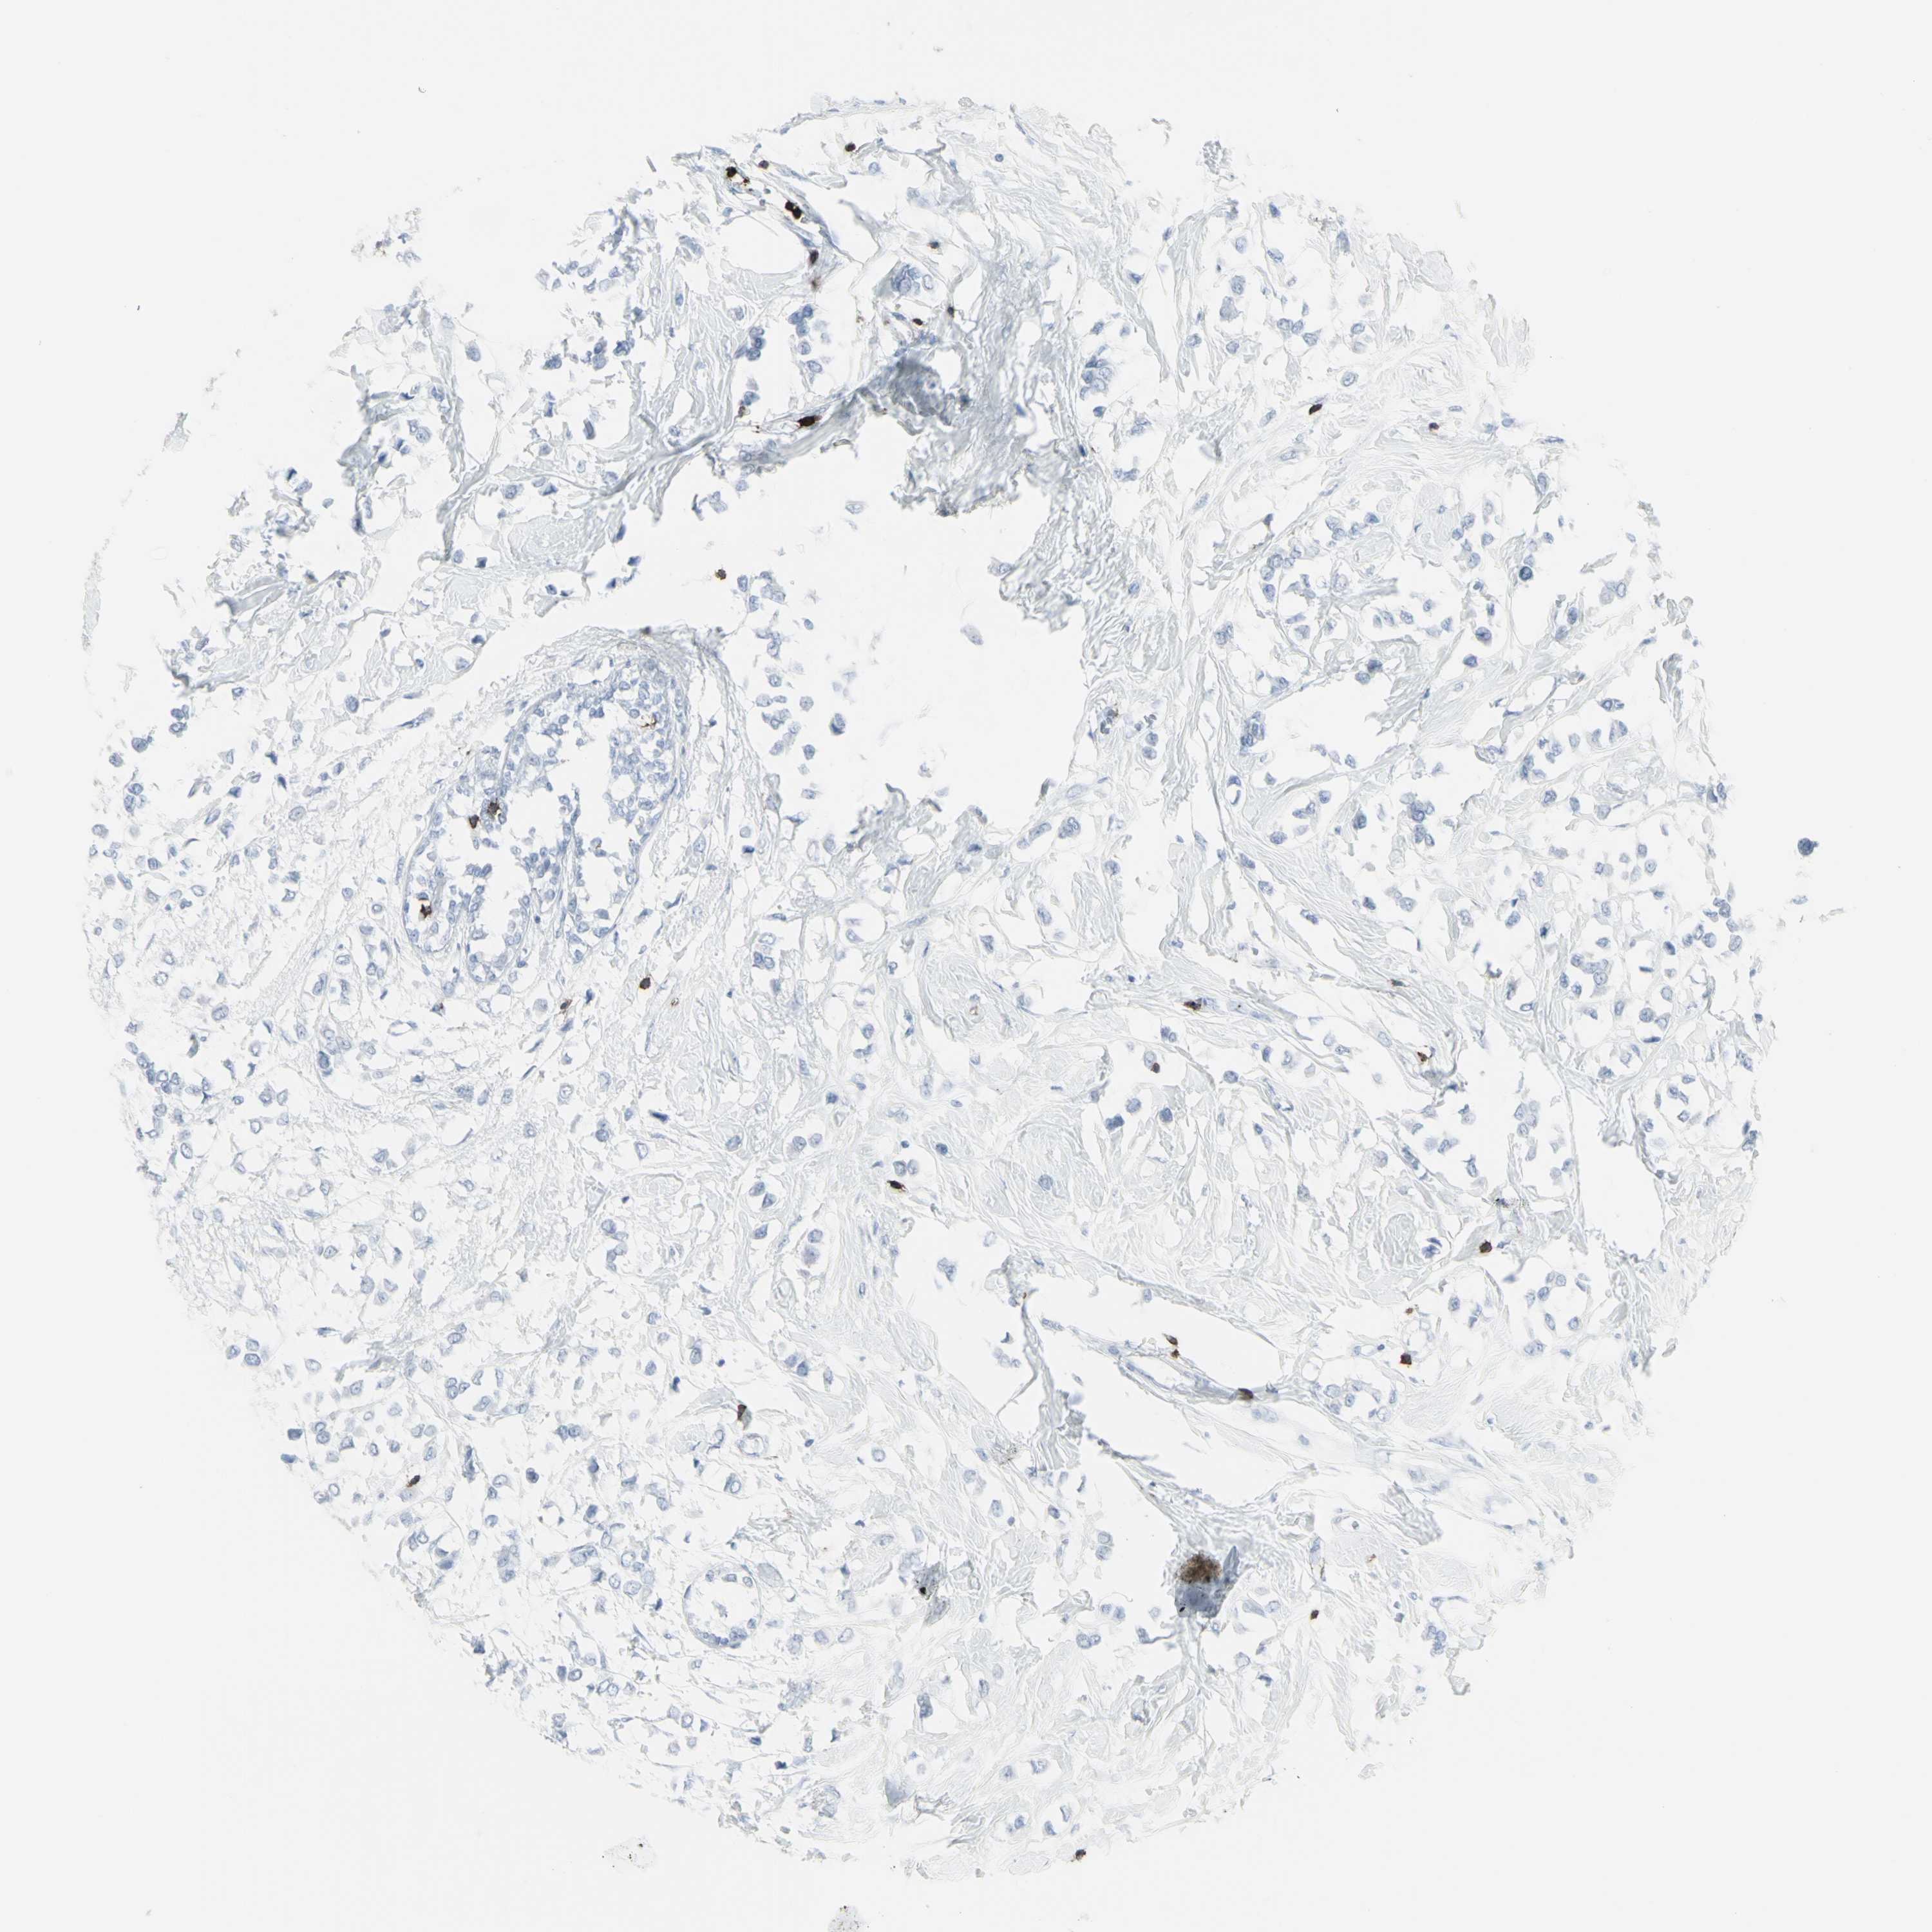

BRCA TCGA BRCA VALIDATION PROTEIN EXPRESSION

ANTIBODIES

AND

VALIDATION